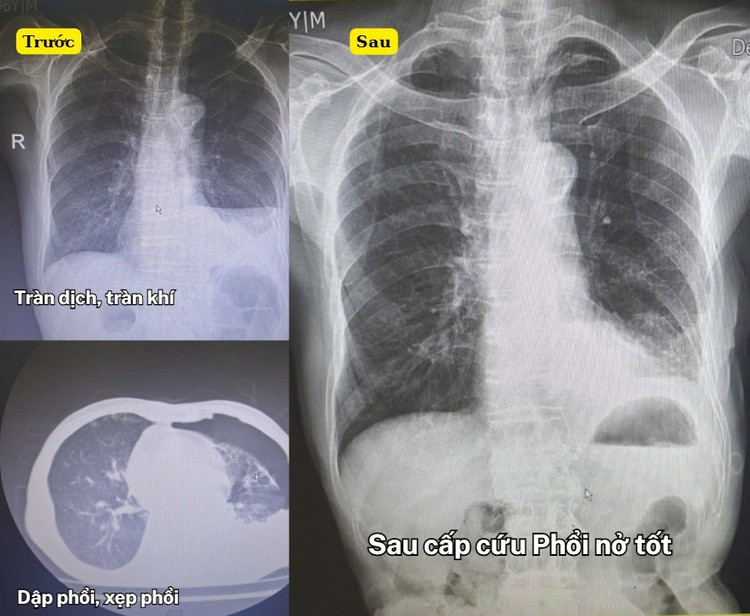

Hình ảnh chấn thương ở phổi của bệnh nhân trước và sau cấp cứu - Ảnh BVCC

Qua thăm khám và kết quả cận lâm sàng, các bác sĩ chẩn đoán: Chấn thương ngực kín, gãy xương sườn 6,7, 8, 9, tràn khí - tràn máu màng phổi, dập thùy dưới phổi trái. Đây là tình huống đặc biệt nguy hiểm, nhất là với bệnh nhân tuổi cao, có nhiều bệnh lý nền, nguy cơ suy hô hấp, đe dọa tính mạng bất cứ lúc nào.

Trước tình hình đó, BS Nguyễn Đức Hoàn, Khoa Ngoại cùng ê-kíp trực đã nhanh chóng triển khai các biện pháp cấp cứu kịp thời: Dẫn lưu dịch, khí màng phổi, giảm áp lực cho phổi, kết hợp trị liệu hô hấp và điều trị tích cực.

Nhờ sự xử trí nhanh trí, chính xác và chuyên môn vững vàng của đội ngũ y, bác sĩ, sau một thời gian điều trị, bệnh nhân đã ổn định, không còn cảm giác đau tức ngực, hô hấp dần cải thiện, sức khỏe hồi phục rõ rệt.